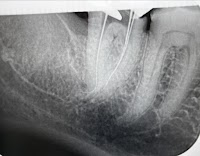

根管治療を受けました。危うく神経を失うところを助けてもらったので感謝しています。普段からハードなトレーニングをしており、歯が命の僕にとって非常に有難い治療でした。また、その根管治療を非常に得意としている先生なので、治療もスムーズでした。歯医者の「痛くない」は世の中で1、2位を争うほど信じられなかった僕の人生で、初めて本当に痛くない治療で感動です。これから探す方、セカンド・オピニオンの方にもオススメできる歯科です。

この度は、10年以上前に失敗した根管治療に対して、保険では治せないところまで、マイクロスコープを使った自由診療で丁寧に治療いただき、ありがとうございました。顕微鏡で細部まで見て治療いただき、また手つきなどで熟練度が伝わり、大変安心感がありました。